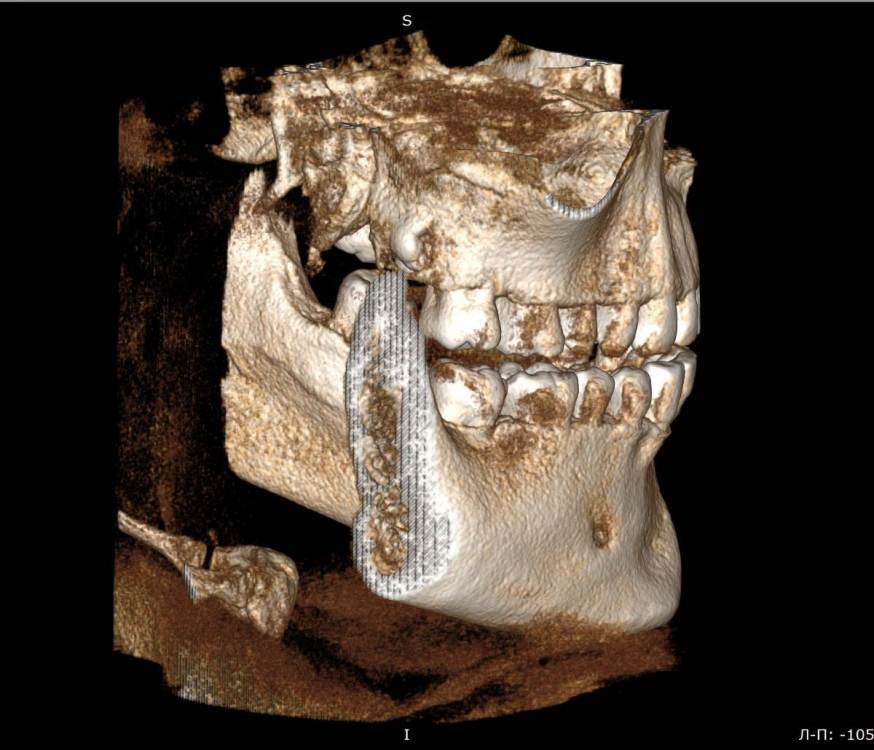

Mnrg Опубликовано 6 июля, 2023 Поделиться Опубликовано 6 июля, 2023 Всех приветствую! Беспокоит правосторонний гайморит и тонзиллит. Сделали КТ, нашли восьмерку, но предложили вместо удаления восьмерки депульпировать шестерку, консилиум сошелся во мнении, что корень перфорирует пазуху и пломба слишком близко к нерву, возможно воспаление. При зондировании между 6 и7 слегка побаливает десна, шестерка не беспокоит, холод чувствует, но не болит. Восьмерку предложили оставить. Спорить не стал, лишь решил собрать воедино мнения специалистов, т.к ближайшие более менее нормальные клиники от 100км. Архив с файлами КТ прикрепил, прошу специалистов глянуть и поделиться мнением, с чего все-таки начать, помочь разобраться.Archive.rar Ссылка на комментарий

wladdX Опубликовано 7 июля, 2023 Поделиться Опубликовано 7 июля, 2023 (изменено) Гайморит у вас совершенно необязательно имеет одонтогенную природу (вызван зубами). Судя по КТ, зуб 16 может быть виновником (а может и не быть). Для уточнения нужна также проверка витальности его пульпы (жив нерв или нет). Если пульпа нежизнеспособна, то этот зуб почти наверняка поддерживает воспалительный процесс в пазухе. Зуб 18 вряд ли нужно трогать. Лежит он себе в кости и пускай, никому он там не вредит. Да он вплотную прилежит к корням зуба 17, но и только. С внешней средой не контактирует. Никакого негативного влияния на соседние зубы он оказывать не должен: формирование корней завершено, потенции к росту и какому-либо движению нет. Удаление зуба 18 в данной ситуации вряд ли оправдано. Процедура не самая простая, но и не запредельной сложности. Изменено 7 июля, 2023 пользователем wladdX Ссылка на комментарий

Mnrg Опубликовано 7 июля, 2023 Автор Поделиться Опубликовано 7 июля, 2023 6 минут назад, wladdX сказал: Гайморит у вас совершенно необязательно имеет одонтогенную природу (вызван зубами). Судя по КТ, зуб 16 может быть виновником (а может и не быть). Для уточнения нужна также проверка витальности его пульпы (жив нерв или нет). Если пульпа нежизнеспособна, то этот зуб почти наверняка поддерживает воспалительный процесс в пазухе. Зуб 18 вряд ли нужно трогать. Лежит он себе в кости и пускай, никому он там не вредит. Да он вплотную прилежит к корням зуба 17, но и только. С внешней средой не контактирует. Никакого негативного влияния на соседние зубы он оказывать не должен: формирование корней завершено, потенции к росту и какому-либо движению нет. Удаление зуба 18 в данной ситуации вряд ли оправдано. Процедура не самая простая, но и не запредельной сложности. Шестерку проверяли холодом - чувствует, не знаю, означает ли это жизнеспособность пульпы, но на холод реагировал немного сильней других зубов. Сегодня открыл КТ программой RadiAntViewer и обнаружил в 3D просмотре визуальные признаки нахождения части восьмерки в краю пазухи. Конечно я не могу утверждать, т.к не врач и насколько понимаю это режим моделирования, но все же выглядит убедительно на мой скромный взгляд. Еще один глупый вопрос, если позволите) Возможно ли в шестерке в одном из трех корней воспаление и нерв разрушен, а другие два при этом будут создавать чувствительность, т.е быть "живыми" или же это фантастика? Деньги запросили немалые для нашего региона за депульпацию (13к) поэтому пытаюсь собрать как можно больше информации прежде, чем принимать решения. Ссылка на комментарий